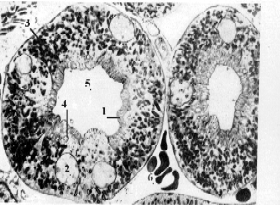

| Электрон- ная микро- фото- графия | а) Электронная микрофотография позволяет разглядеть только что упомянутые структуры: пиноцитозные пузырьки (4), придающие цитоплазме “вспененный” вид; микроворсинки (1), создающие щёточную каёмку, | Полный размер |

многочисленные митохондрии (3), концентрирующиеся, в основном, в базальной части клеток и отчасти обуславливающие базальную исчерченность. б) Кроме того, на снимке отмечены ядра (2) эпителиоцитов (имеющие округлую форму), просвет (5) канальца и кровеносный капилляр (6). | ||

| Связь строения с функцией | а) Напомним: в проксимальных извитых канальцах происходит активная реабсорбция большей части оказавшихся в фильтрате веществ. б) Этой высокой функциональной активности соответствуют отмеченные особенности строения: щёточная каёмка и складчатость увеличивают поверхность, через которую переносятся реабсорбируемые вещества, а митохондрии обеспечивают энергией активный транспорт. |